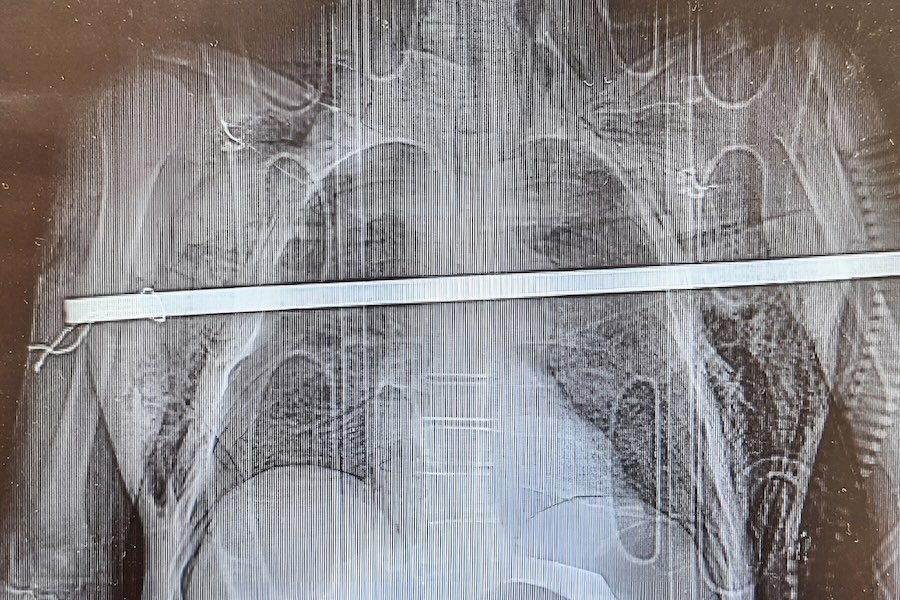

V nemocnici se tým lékařů a sester několika klinik a oddělení pustil do práce zhruba o půl osmé večer. Před operací pacienta důkladně vyšetřili. Kromě rentgenu a cétéčka bylo nutné i endoskopické vyšetření. „Jeho pomoc pro nás byla zásadní. Věděli jsme díky tomu, které orgány jsou poškozené a do jaké míry. Pan Kučera měl obrovské štěstí, protože tyč prošla hrudníkem, třetím mezižebřím, propíchla obě dvě plíce a v podstatě ležela na aortě. Dotkla se i jícnu, ale neperforovala ho. Minula těsně i plicní hily, tedy místa, kde vstupují cévy do plic. Stačilo několik milimetrů a už by mu nebylo pomoci,“ popsal kardiochirurg Martin Kaláb.